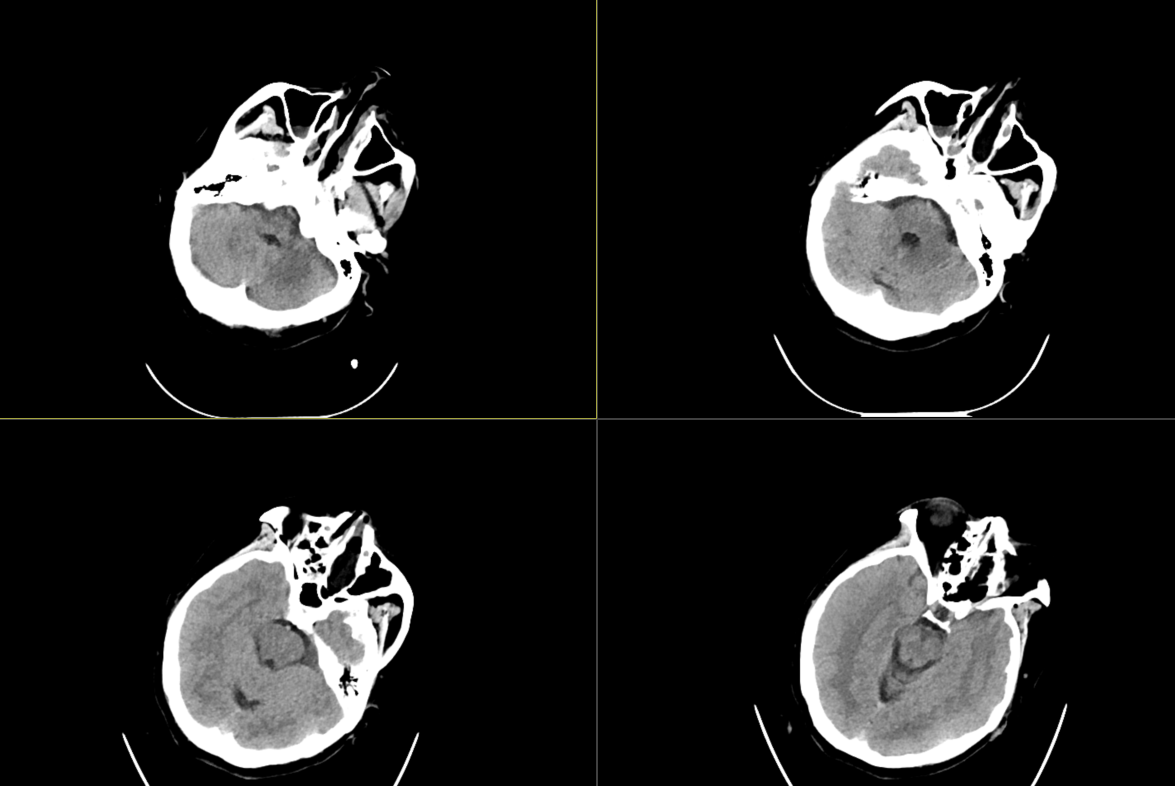

术前影像:

术前影像: